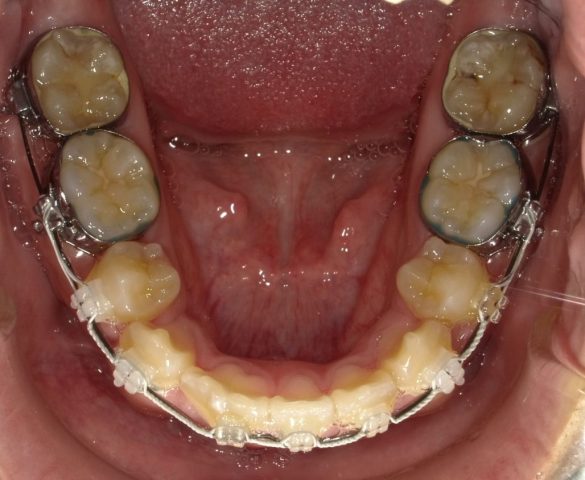

【下顎咬合面観】

2023年1月

| 治療方法・治療内容 | 4本抜歯・フルブラケット・ストレートワイヤーテクニック |